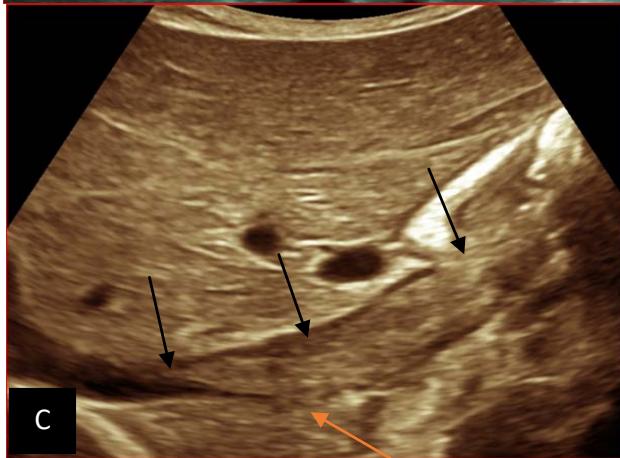

Figure 5: Abdominopelvic ultrasound control after 6 courses of chemotherapy in the same 3 year old patient with a ruptured left renal nephroblastoma; Images A, F, G, and H: show regression of the solid, endo and exo renal, left nephroblastoma mass treated with 6 courses of chemotherapy (current volume 430 ml vs) Images: B, C, and: show persistence of thrombotic permeation pan vena cava and ipsilateral renal. Image E: shows a volumetric regression of the intra-lesional hematic collection, at the tumor rupture estimated at 34.49 ml VS, Image I: represents the right kidney in B mode which is of normal echoculture. Source: Dr. Frederick Tshibasu Tshienda database.